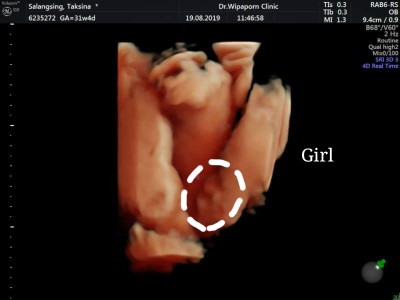

หนูมีกลีบค้าา😂

กลีบเต็มๆคะ

เป็นกลีบจ้าาาา